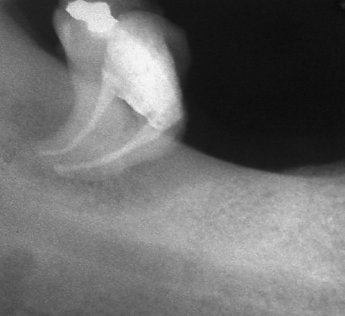

Добре пролекувани зъби

Периодонтити